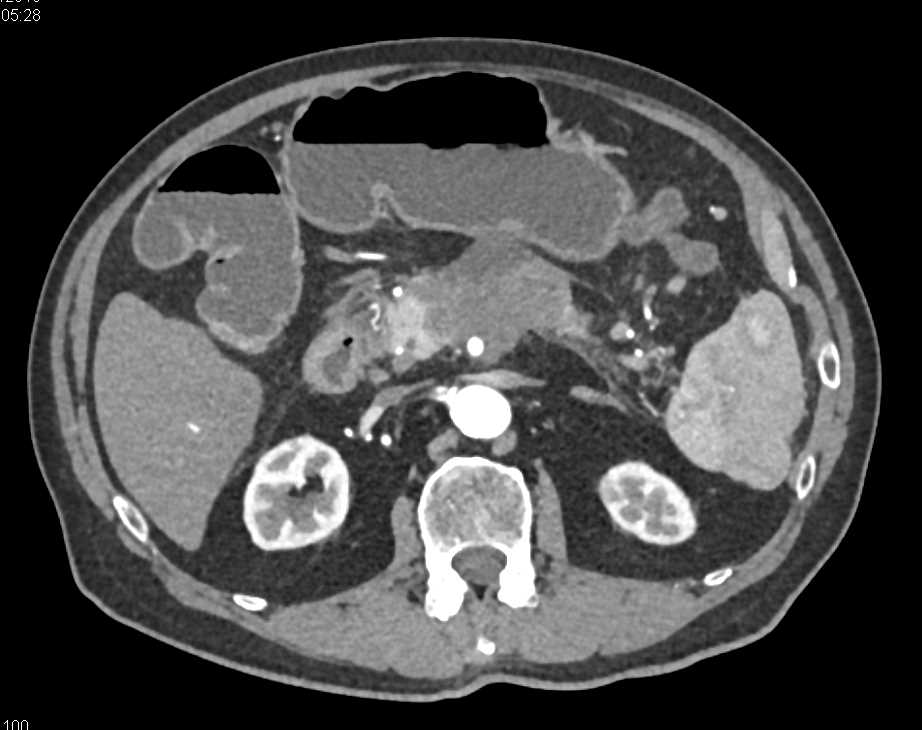

Adenocarcinoma Body of Pancreas